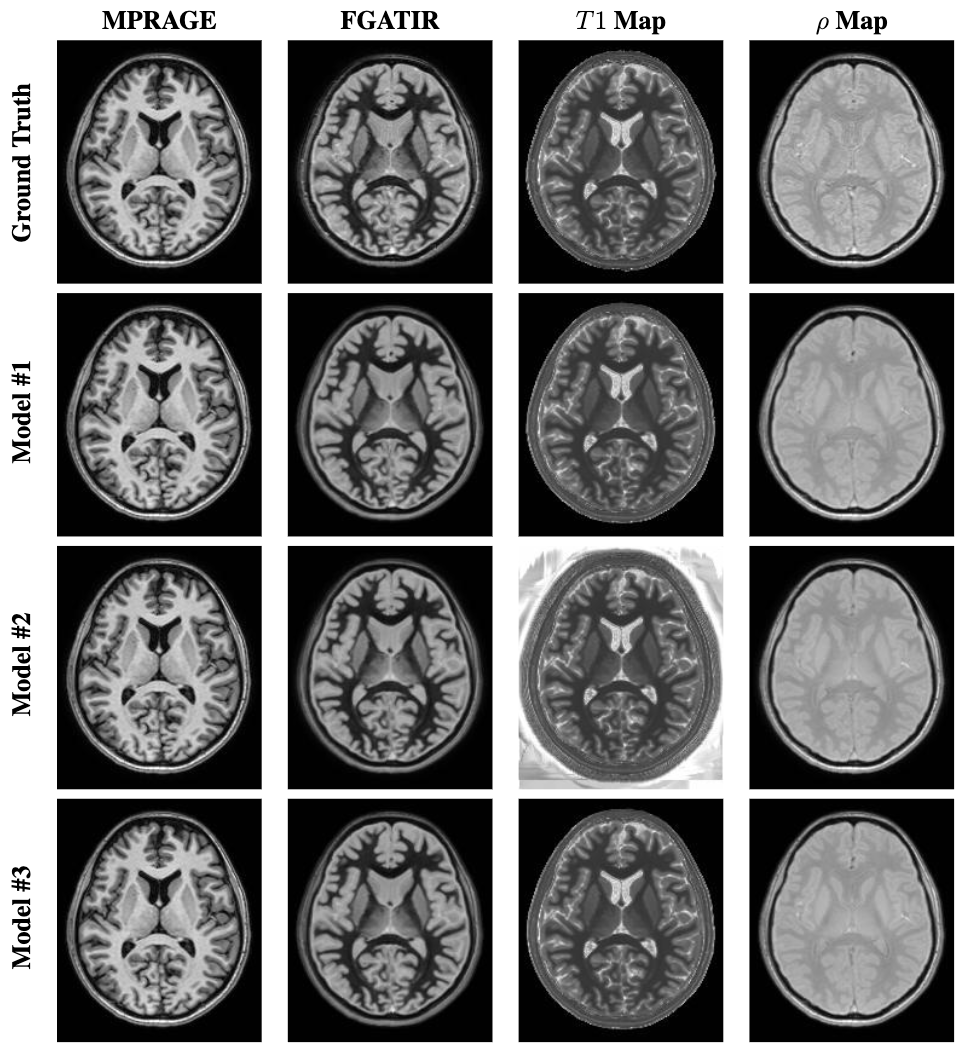

First, we tested our models on the in-domain test set (N=23N=23). An illustrative example of the predicted T1T1 and ρ\rho parameter maps, along with the corresponding synthetic MPRAGE and FGATIR images, is shown in Fig. 6 with the corresponding ground truth images (the acquired images and computed parameter maps). Figure 7 features a thalamic cross-sectional intensity profile of the MPRAGE and FGATIR ground truth and prediction images. This provides a visual means of evaluating the alignment and fidelity of the predicted images relative to the ground truth.

Refer to caption

Figure 6: Ground truth images of a testing subject with the prediction images using the proposed SyMTIC models.

Table 1 reports the PSNR and SSIM for each image synthesized from each model. To ensure the evaluation focuses on meaningful image content, we excluded background voxels from the error calculations. Among the three models, we observed similar performances but Model #2 give us the highest quantitative results for the two synthetic images and two parameter maps computed by SyMTIC. In Table 1, the paired Wilcoxon signed-rank test with Bonferroni correction was used to determine statistical significance between the three models and the reference images. Model #2 showed statistically significant improvements (p <0.001<0.001) over both Model #1 and Model #3 for PSNR and SSIM in MPRAGE and T1T1 maps and only SSIM in FGATIR. For the ρ\rho map, while Model #1 demonstrated lower variability, Model #2 achieved the highest mean SSIM, which was statistically better (p <0.05<0.05) than Model #1. These results support the overall superiority of Model #2 for synthesizing high-fidelity parameter maps and images.